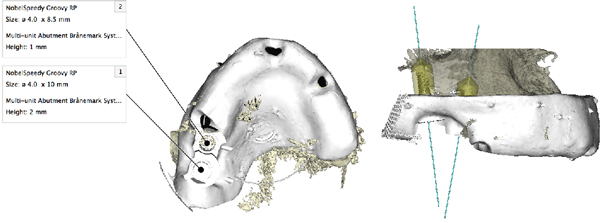

⑮ガイデットサージェリー(前顎に及ぶ歯槽骨非薄)

症例⑮ガイデッドライブオペ(オペ時間約3分)